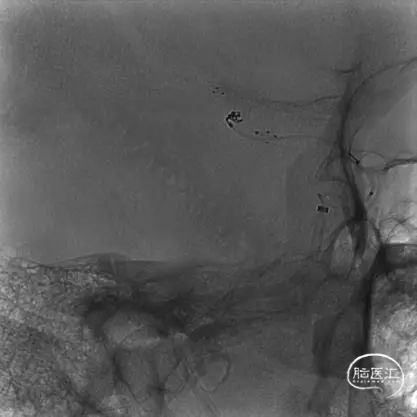

栓塞微导管及支架微导管到位后,首先使用弹簧圈2*3一枚试行成篮。由于瘤颈太宽,弹簧圈溢出动脉瘤。故部分释放弹簧圈后,先行完全释放支架,再继续释放弹簧圈栓塞。

术中可见Atlas支架定位精准,支架释放过程中,栓塞导管没有受到任何影响,待支架完全打开后,将首枚弹簧圈全部释放。

经SL-10微导管送入1.5*3弹簧圈进行填塞,可见部分弹簧圈突入支架与瘤颈处的载瘤动脉之间。突出的弹簧圈形成基座,确保瘤颈处得到栓塞而不复发。

继续使用1.5*2、1*1两枚弹簧圈收尾。可见Atlas支架网眼较小,完全可以阻挡小弹簧圈通过网眼进入载瘤动脉。